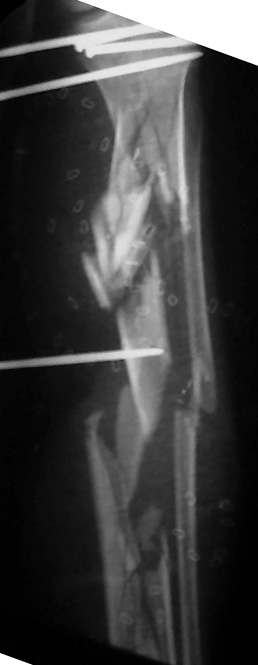

I would appreciate treatment suggestions.My patient is a 30 year old with a very comminuted tibia fracture 6 weeks ago.It was grade 3B open. Initial treatment included irrigation, debridementClick images to enlarge.

and a hybrid external fixator including femur, tibia and foot. Screwswere placed in the plateau and plafond and a free flap plus STSG. Theskin is ok but atrophic. The femoral pins were removed and knee motionstarted at 6 weeks. There is no sign of callus. There is one pin inthe one large fragment of the diaphysis. All the pieces are lined upreasonably well. The XF pins are ok. Suggestions? Thank you.